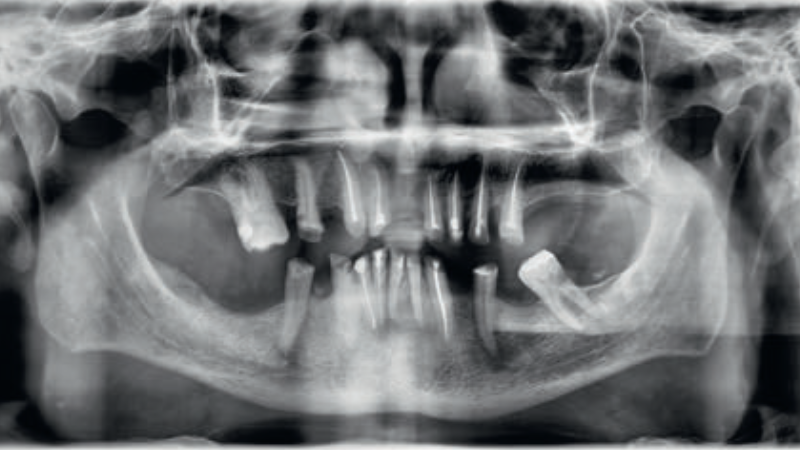

Streszczenie: W artykule opisano przypadek odbudowy tkanek zębów w szczęce i żuchwie przy pomocy wkładów koronowo-korzeniowych metalowych lanych, koron metalowo-porcelanowych, mostu metalowo-porcelanowego oraz protez szkieletowych. Przeprowadzone leczenie pozwoliło na pełną rehabilitację narządu żucia, poprawę estetyki twarzy, uśmiechu i zębów oraz pozytywnie wpłynęło na komfort psychiczny pacjenta.

Summary: The article presents a case of maxillary and mandibular dental tissue reconstruction as well as the restoration of missing teeth using cast metal posts, metal-porcelain crowns, a metal-porcelain bridge and skeletal dentures. The performed treatment has enabled full rehabilitation of the masticatory system and improved facial, smile and dental aesthetics, and positively influenced the patient’s psychological comfort.